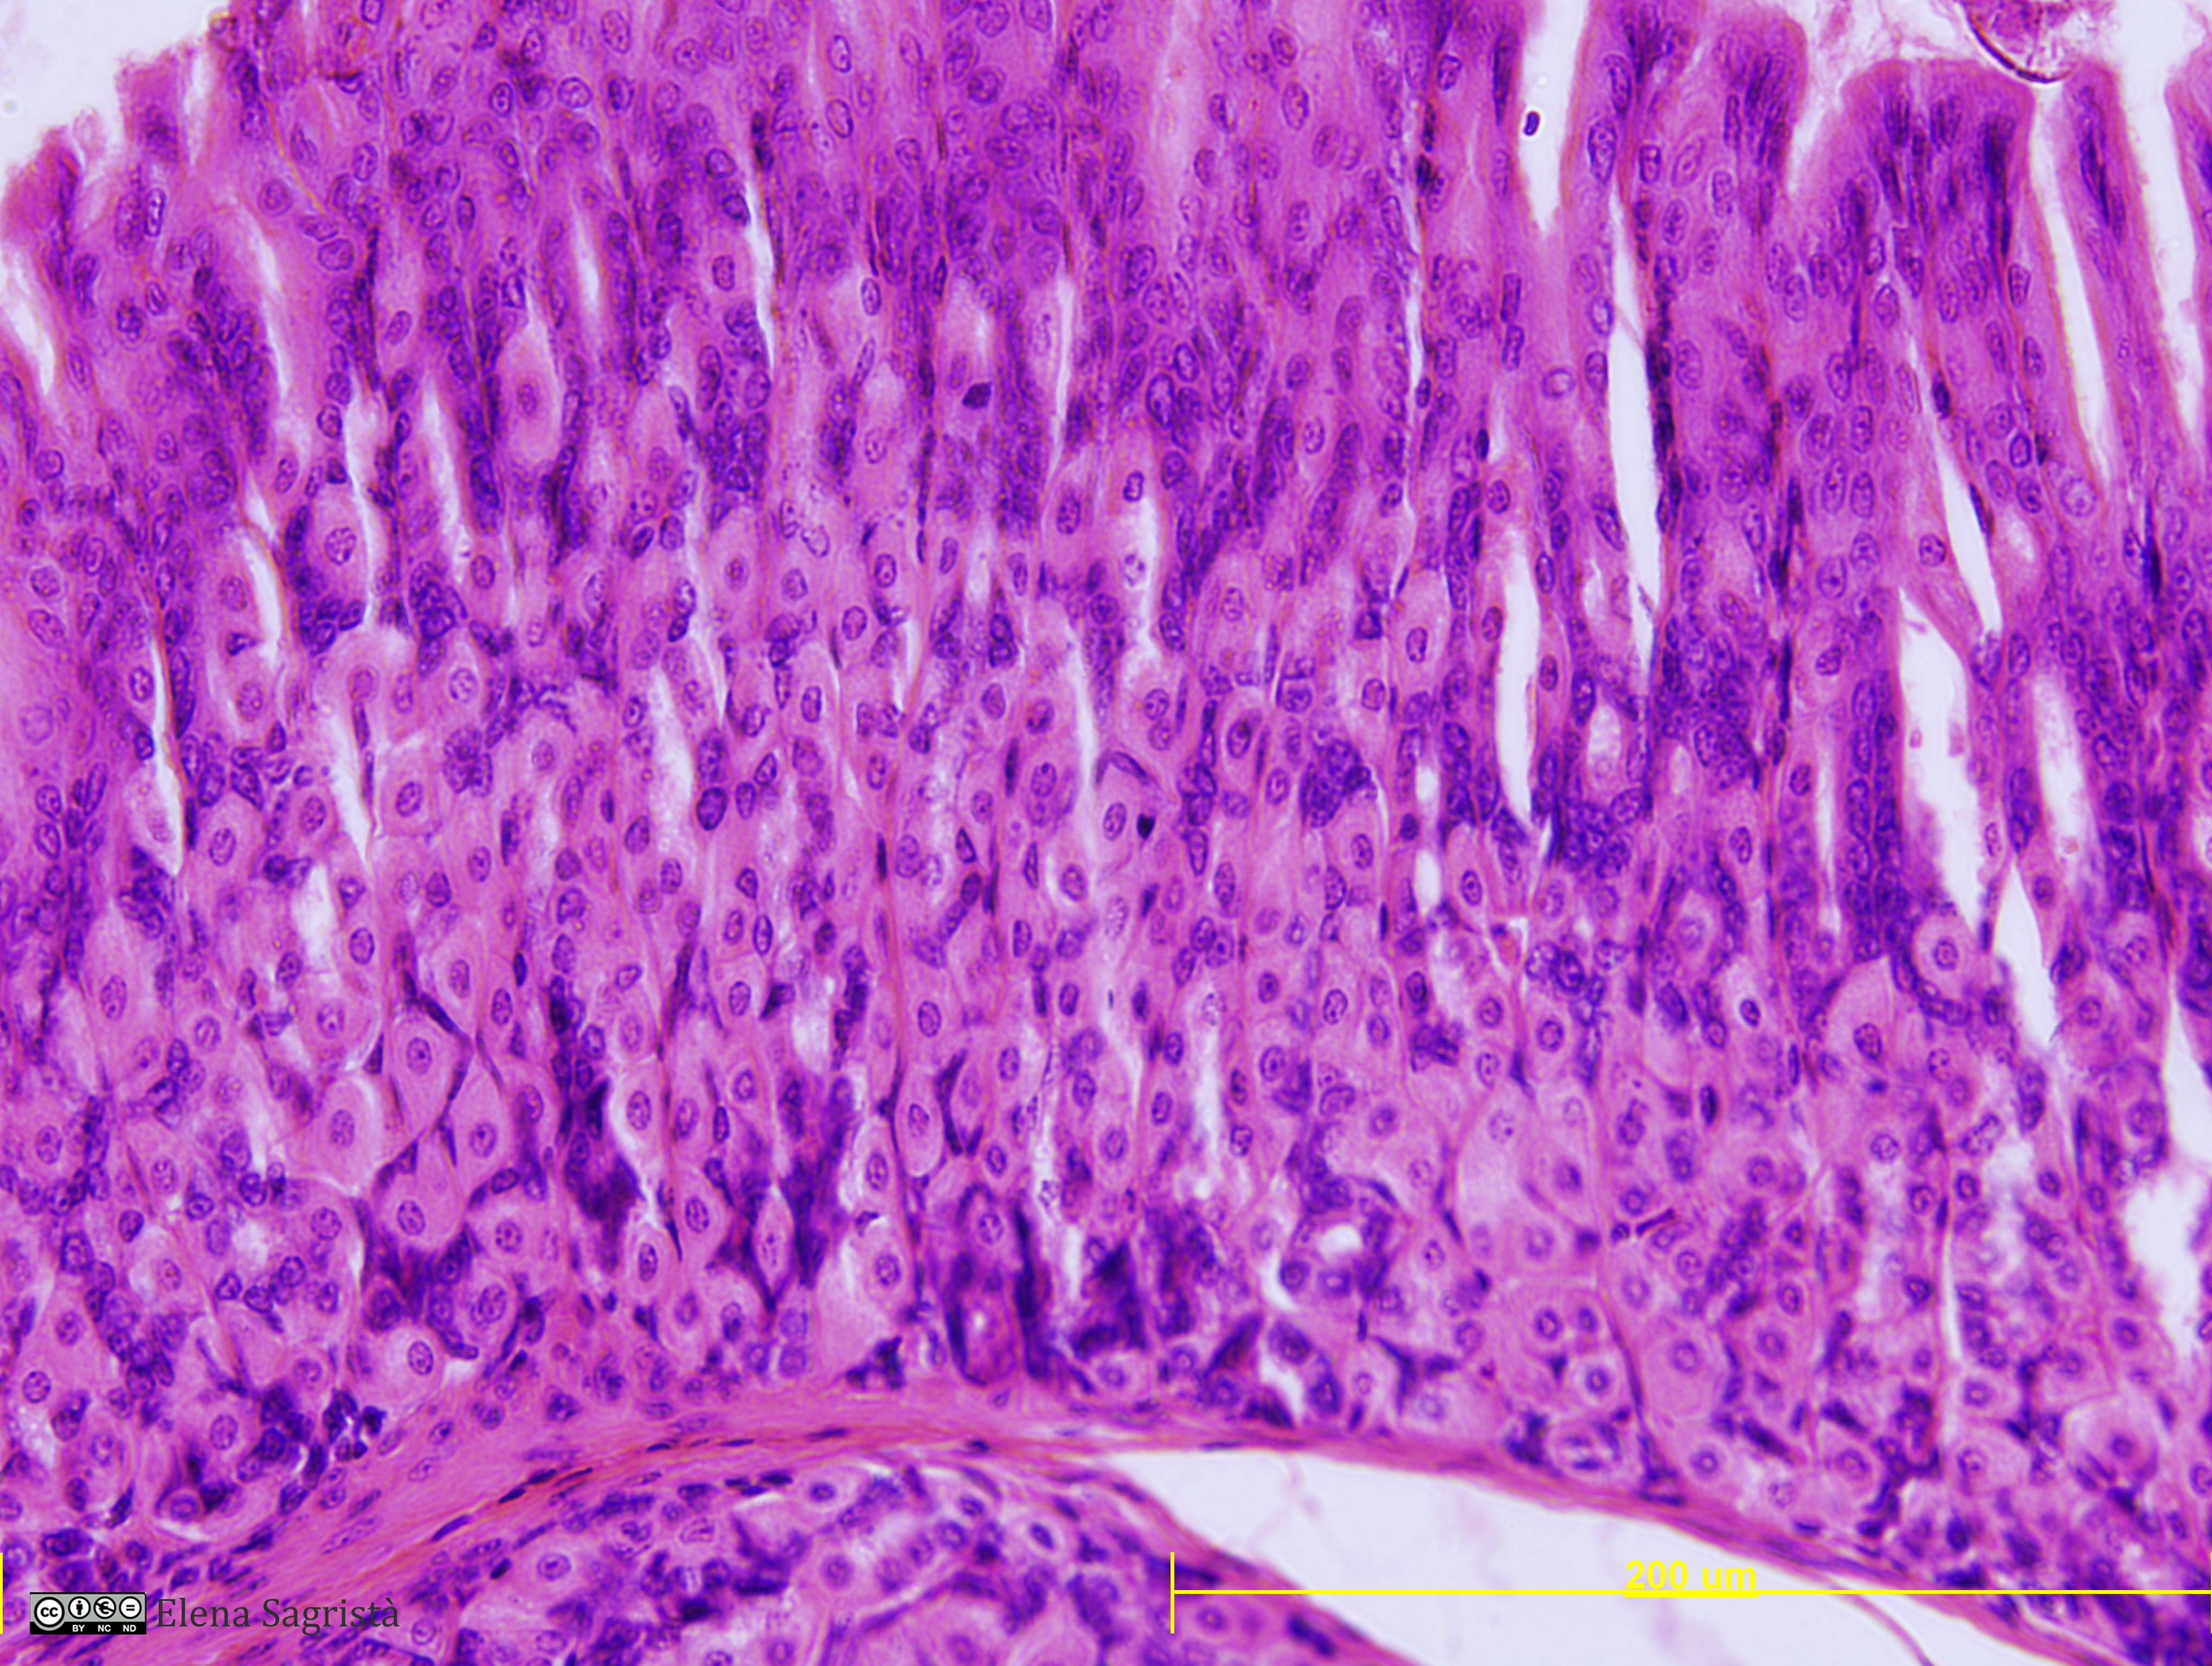

Histologia imatges: 16 Estòmac

Imatges de preparacions histològiques d'Estómac. Microscopia òptica.